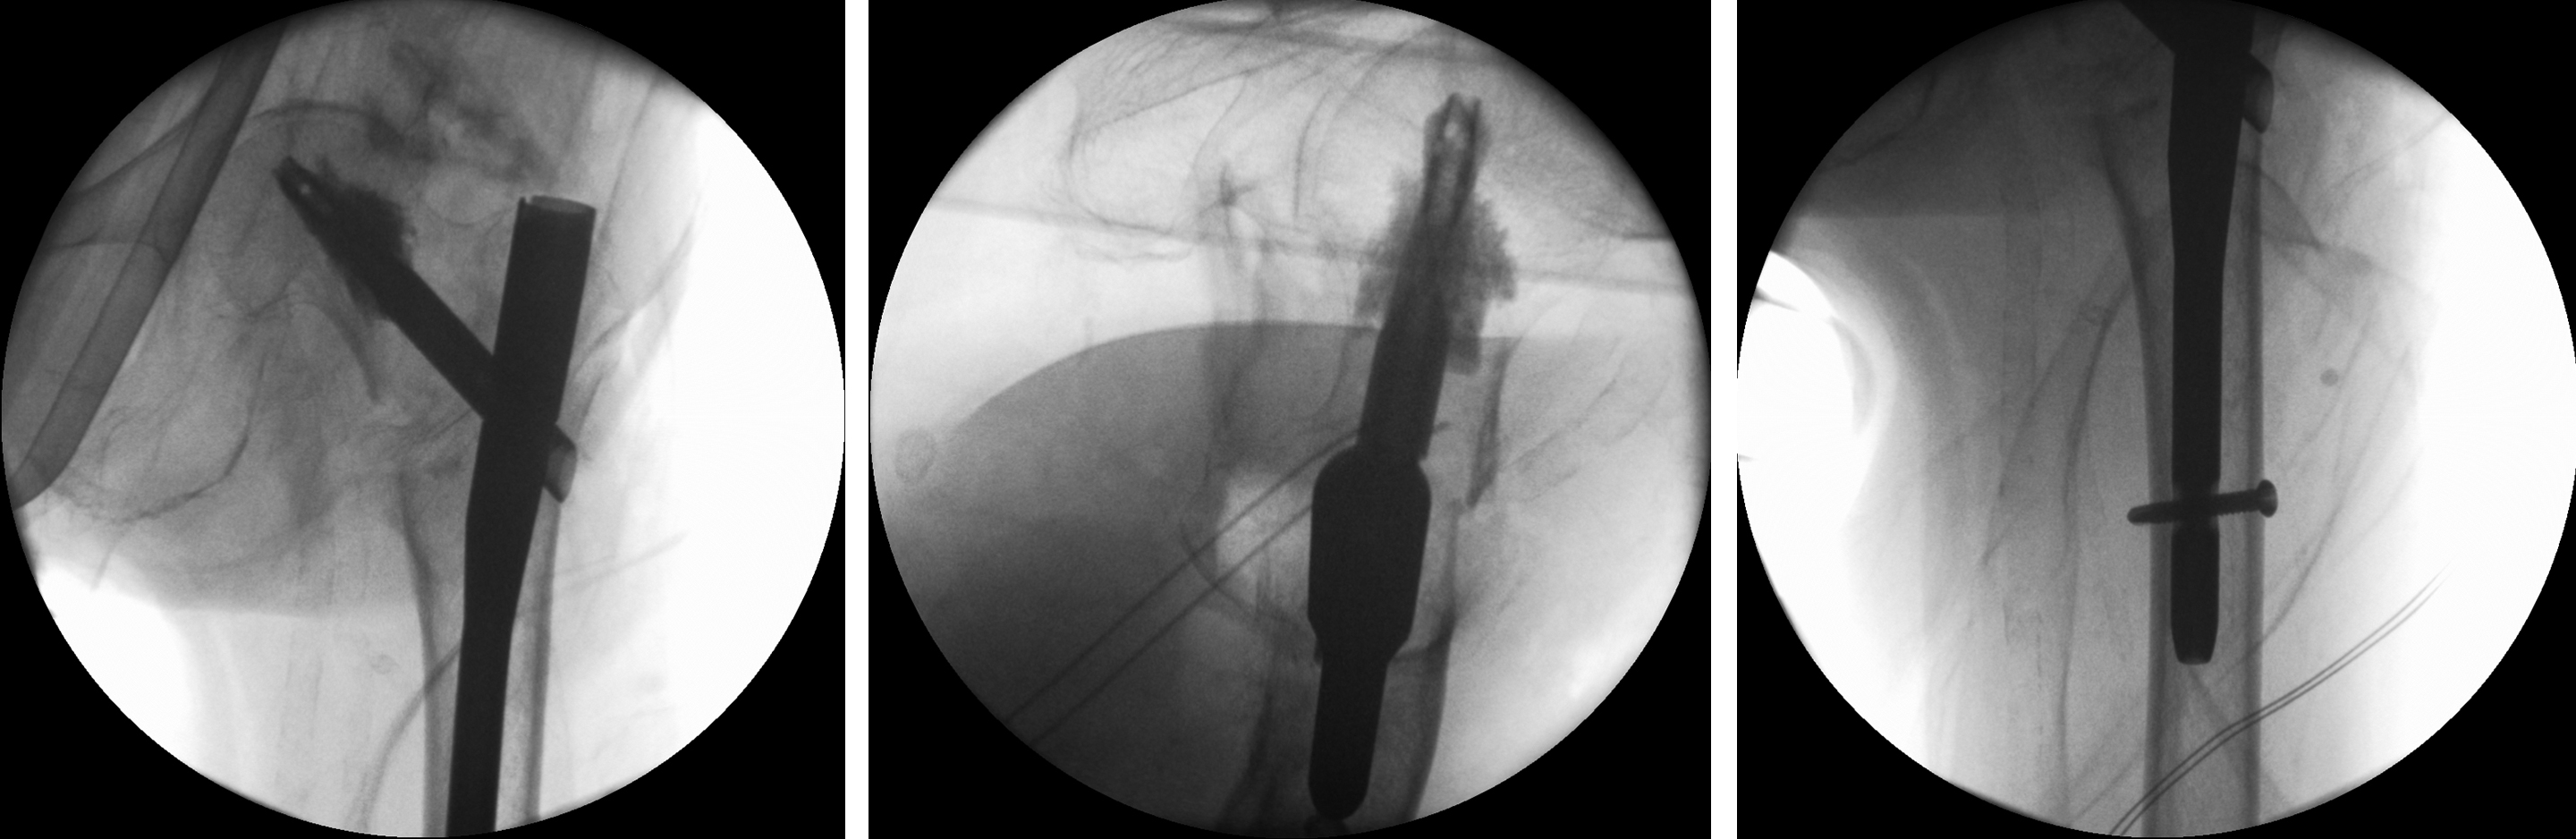

An 83-year-old female patient sustained a 31-A.2.2 fracture of the right proximal femur after a fall at home (Figs 1-2). Intraoperative and postoperative images are shown (Figs 3-5).